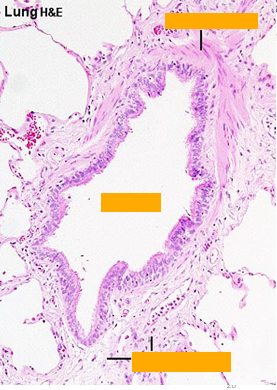

Lung

Alveolar epithelium

Alveoli

Arrow = Interalveolar septum

Lung alveoli and interalveolar septea